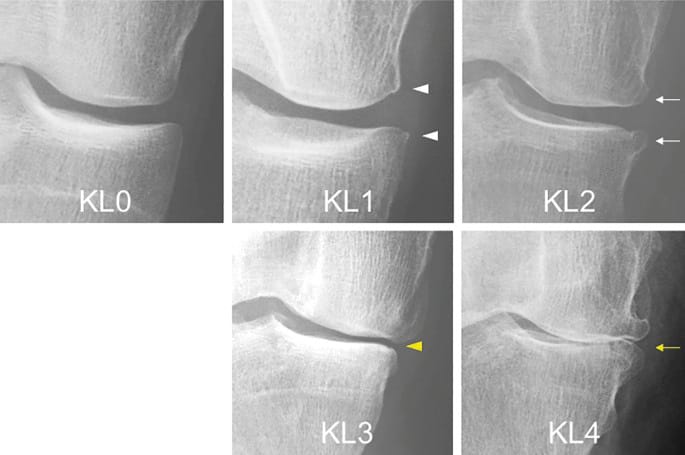

Appropriate patient selection represents a fundamental determinant of TKA success [3] Connelly JW, Galea VP, Rojanasopondist P, Nielsen CS, Bragdon CR, Kappel A, et al. Which Preoperative Factors are Associated with Not Attaining Acceptable Levels of Pain and Function After TKA? Findings from an International Multicenter Study. Clin Orthop Relat Res 2020;478:1019–28. https://doi.org/10.1097/CORR.0000000000001162. (Figure 1). Evidence demonstrates that patients with severe Kellgren-Lawrence Grade 4 bone-on-bone osteoarthritis (AO) consistently achieve superior outcomes compared to those with early-stage disease [4], Polkowski GG, Ruh EL, Barrack TN, Nunley RM, Barrack RL. Is pain and dissatisfaction after TKA related to early-grade preoperative osteoarthritis? Clin Orthop Relat Res 2013;471:162–8. https://doi.org/10.1007/s11999-012-2465-6.[5] Leppänen S, Niemeläinen M, Huhtala H, Eskelinen A. Mild knee osteoarthritis predicts dissatisfaction after total knee arthroplasty: a prospective study of 186 patients aged 65 years or less with 2-year follow-up. BMC Musculoskelet Disord 2021;22:657. https://doi.org/10.1186/s12891-021-04543-8.. This pattern is reported in treatment failure analyses following TKA, where it has been demonstrated that up to 50% of patients experiencing unexplained post-TKA pain without identifiable diagnosis had mild preoperative osteoarthritis (KL 1-2) [4] Polkowski GG, Ruh EL, Barrack TN, Nunley RM, Barrack RL. Is pain and dissatisfaction after TKA related to early-grade preoperative osteoarthritis? Clin Orthop Relat Res 2013;471:162–8. https://doi.org/10.1007/s11999-012-2465-6.. These findings translate to a 4.2-fold increase in dissatisfaction rates and persistent pain among patients with minimal radiographic OA disease [5] Leppänen S, Niemeläinen M, Huhtala H, Eskelinen A. Mild knee osteoarthritis predicts dissatisfaction after total knee arthroplasty: a prospective study of 186 patients aged 65 years or less with 2-year follow-up. BMC Musculoskelet Disord 2021;22:657. https://doi.org/10.1186/s12891-021-04543-8..

Functional outcomes further support this relationship, as patients with severe OA show superior improvement, exceeding those with mild disease [6] Meding JB, Ritter MA, Faris PM, Keating EM, Harris W. Does the preoperative radiographic degree of osteoarthritis correlate to results in primary total knee arthroplasty? J Arthroplasty 2001;16:13–6. https://doi.org/10.1054/arth.2001.16501.. Additionally, KL Grade 4 patients report significantly lower pain levels at 12-month follow-up compared to the lower-grade counterparts [7] Riis A, Rathleff MS, Jensen MB, Simonsen O. Low grading of the severity of knee osteoarthritis pre-operatively is associated with a lower functional level after total knee replacement: a prospective cohort study with 12 months’ follow-up. Bone Joint J 2014;96-B:1498–502. https://doi.org/10.1302/0301-620X.96B11.33726..

TKA performed on minimally damaged knees may result in persistent implant awareness. These findings underscore that evidence-based patient selection according to disease severity constitutes a critical factor in optimizing TKA outcomes and surgical success rates.